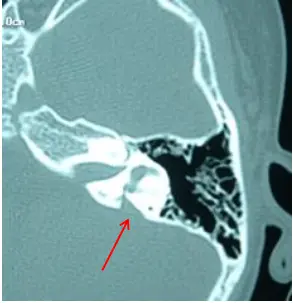

- 大前庭水管综合征的特征性波形——声诱发短潜伏期负反应(ASNR)

大部分患者有进行性或波动性听力下降

ASNR 存在的同时波 I 通常分化不好,不能将其与正常的波 II 的波谷混淆。